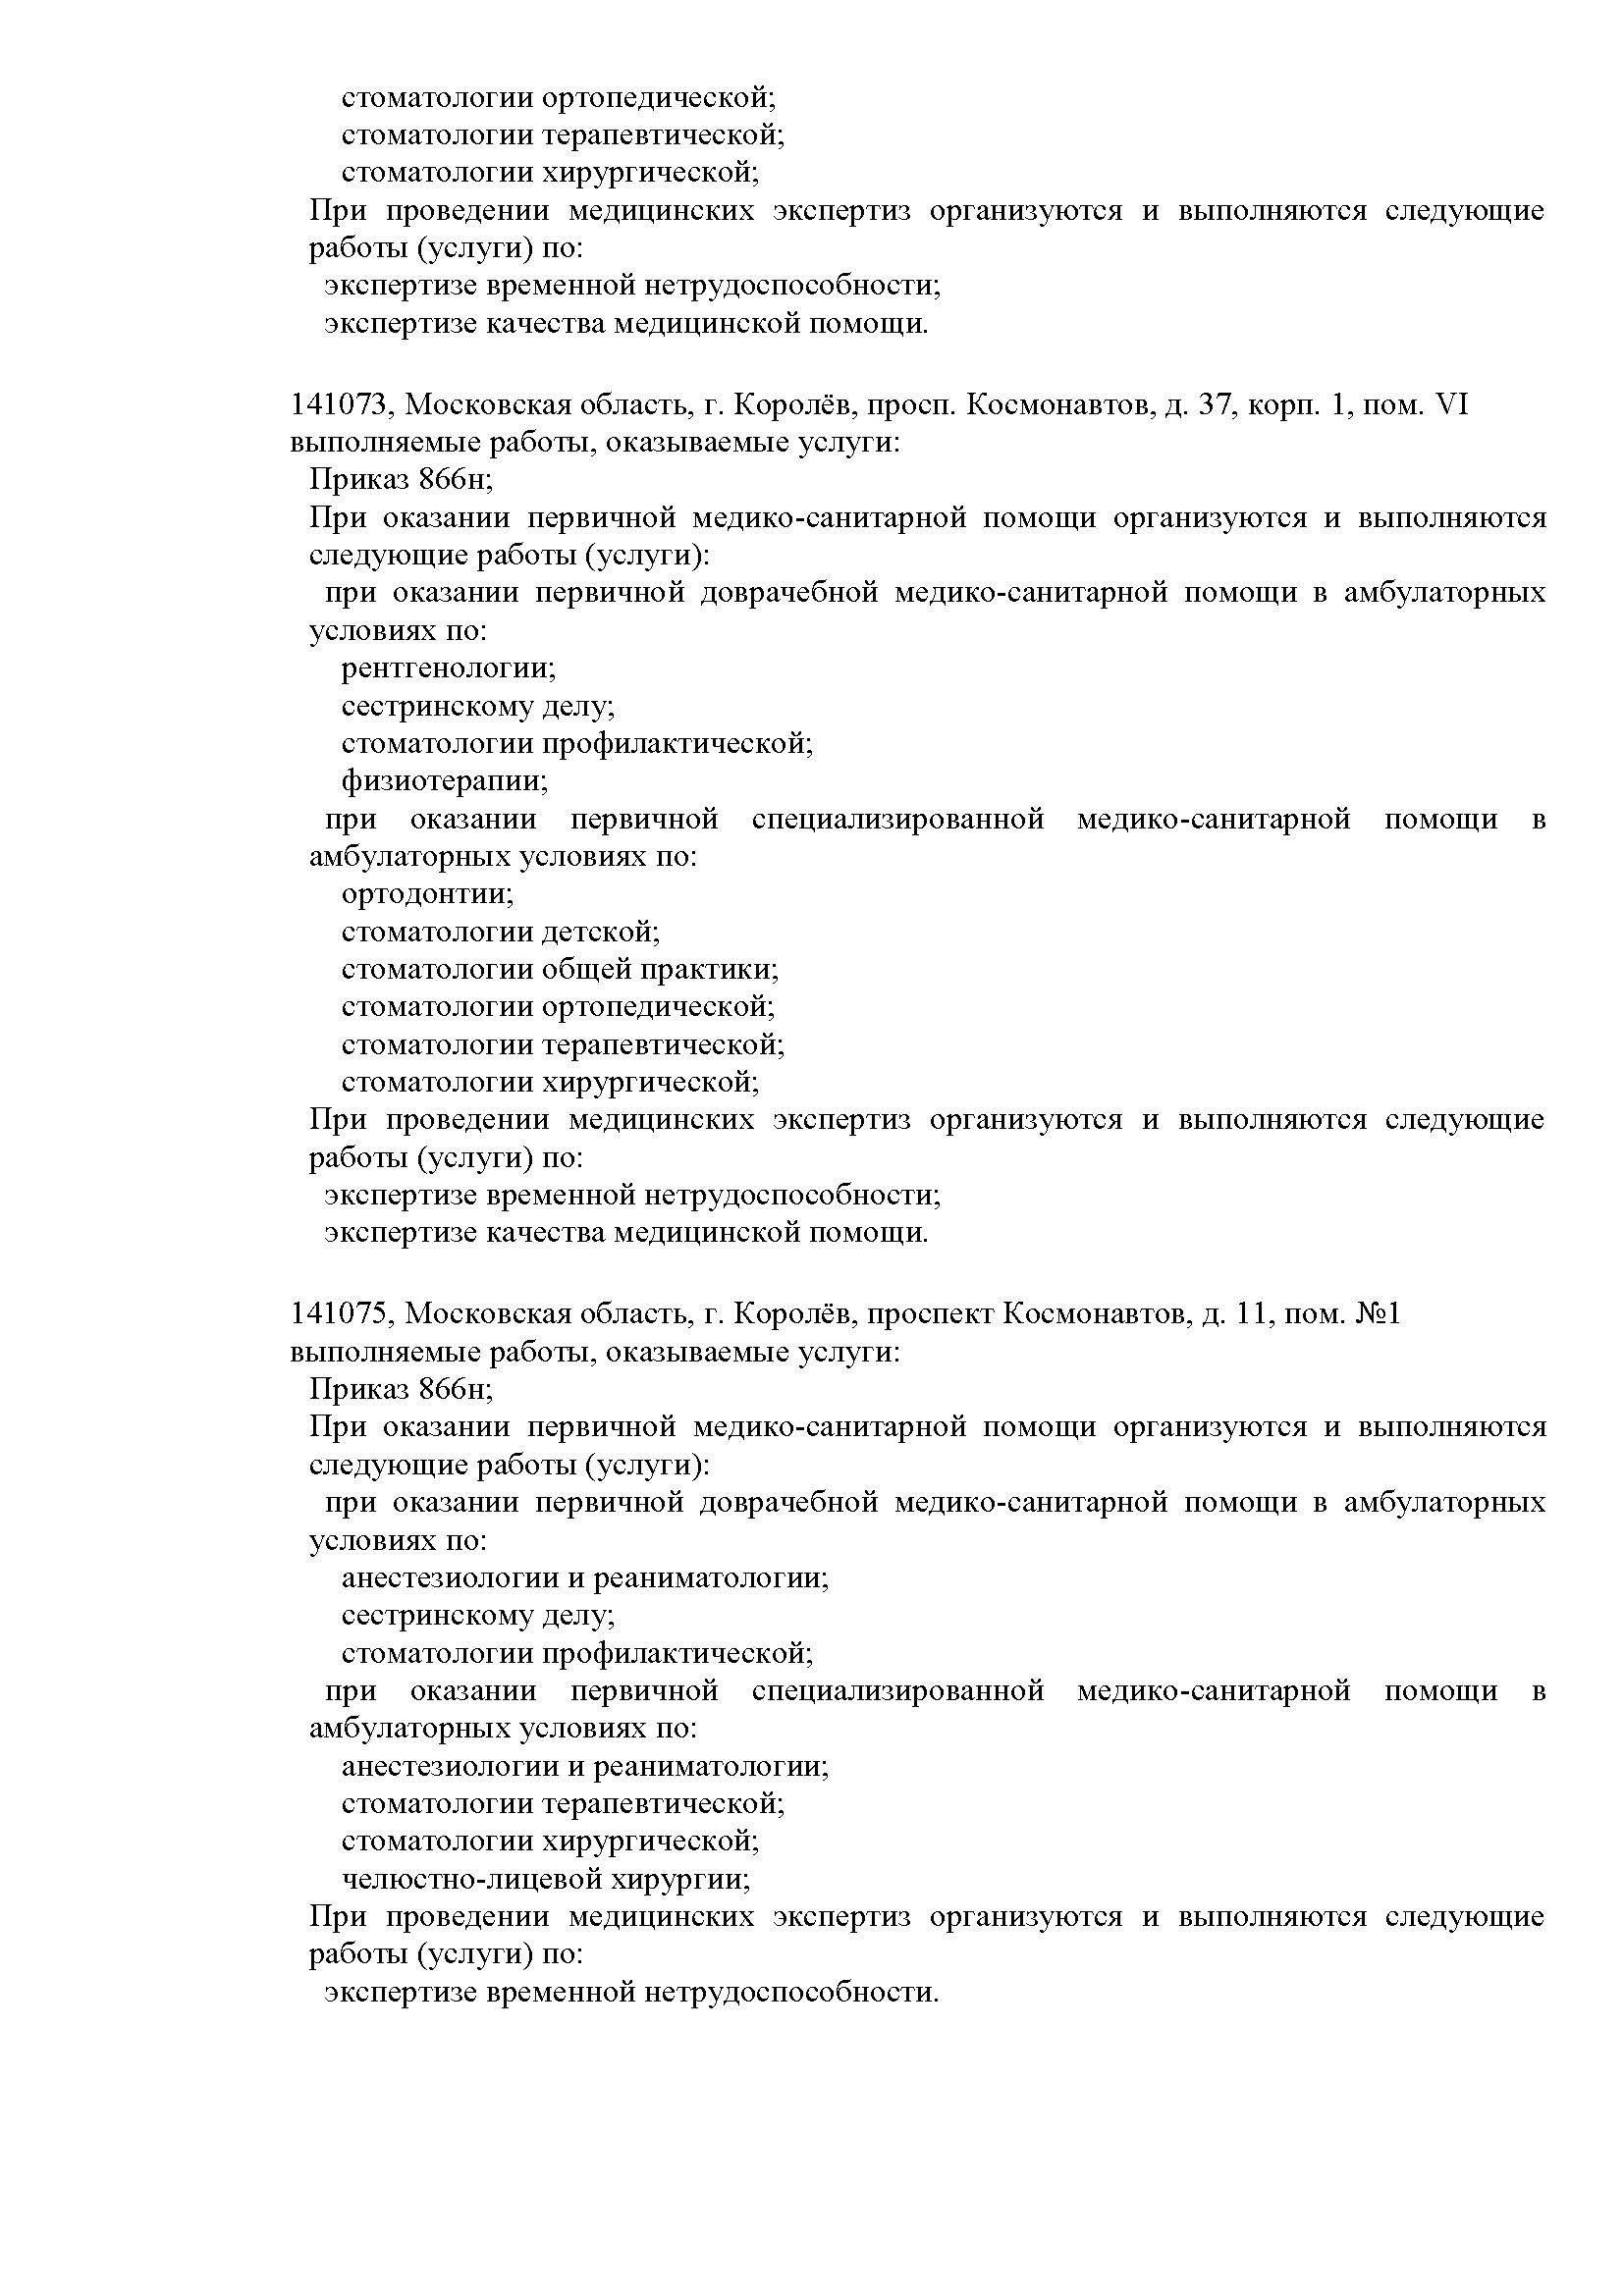

Наши лицензии